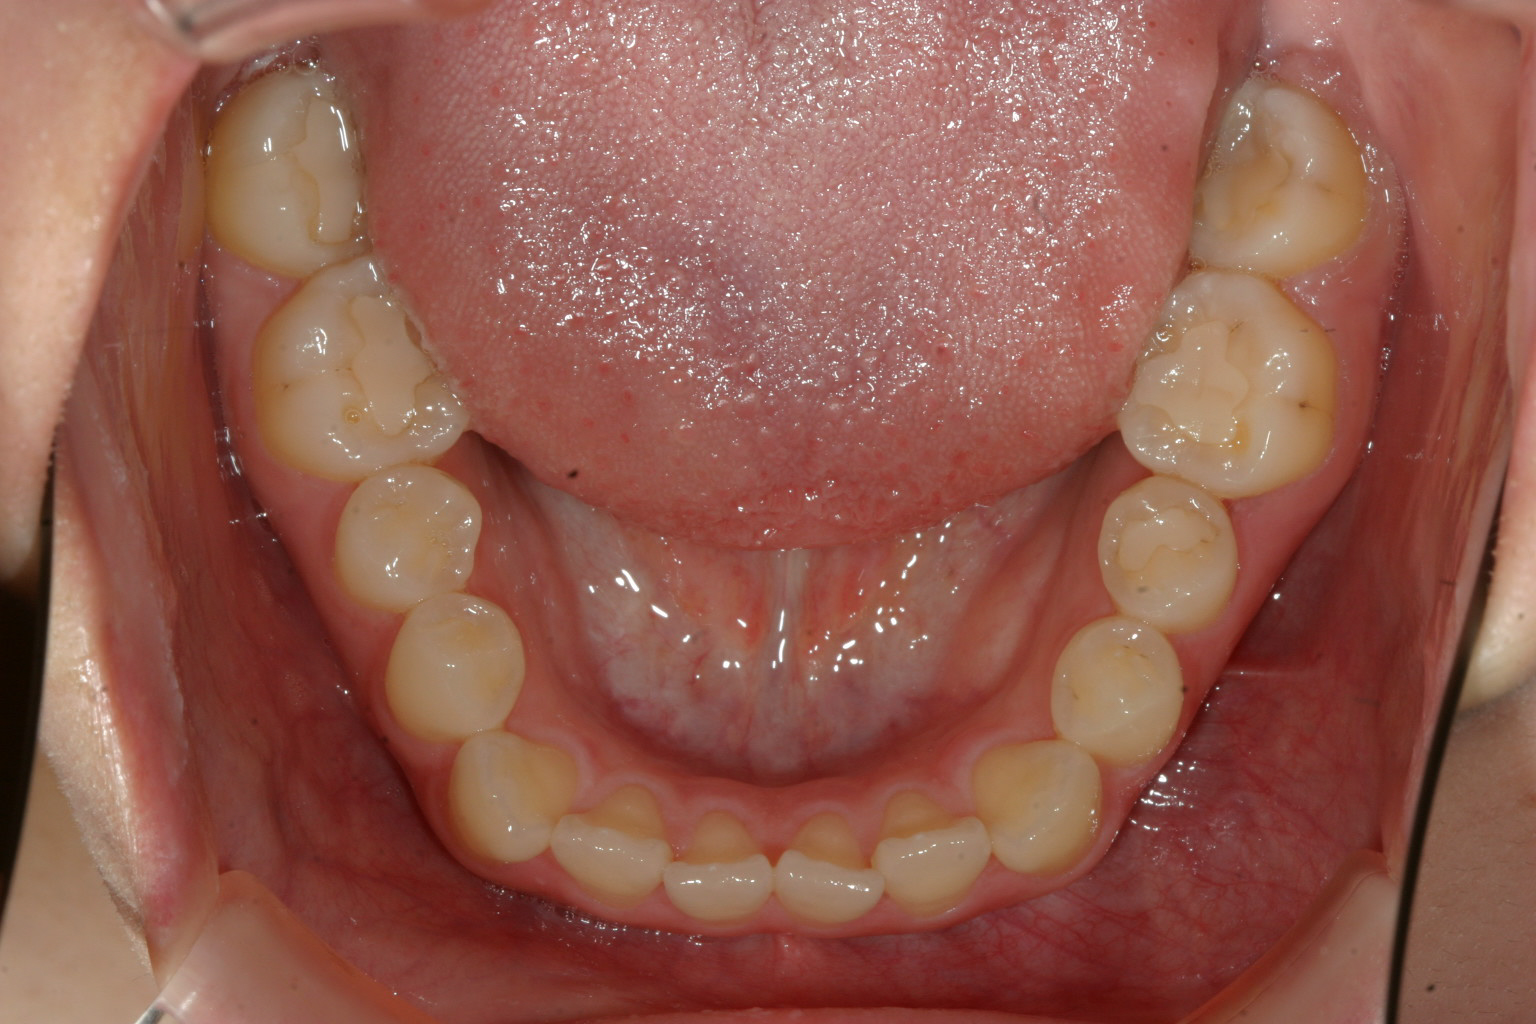

下顎は強いて問題ないですね~